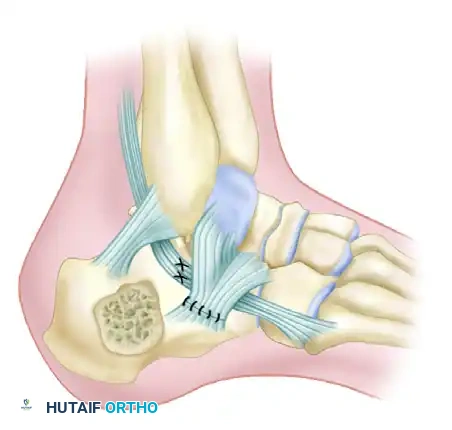

For patients requiring surgical intervention for malunion, the technique described by Braly, Bishop, and Tullos provides an excellent framework for lateral decompression and realignment:

Incision: Make an incision just plantar to the course of the peroneal tendons.

Nerve Decompression: Carefully identify and decompress the sural nerve, which is often encased in scar tissue.

Tenolysis: Incise the inferior extensor retinaculum and perform a thorough peroneal tenolysis.

Ligament Release: Transect the calcaneofibular ligament to fully expose the lateral wall of the calcaneus.

Osteotomy: Perform a lateral calcaneal osteotomy to resect the impinging lateral wall exostosis.

Tendon Lengthening: If the peroneal tendons are contracted or anteriorly dislocated, perform a Z-lengthening procedure.

Reconstruction: Repair or reconstruct the inferior retinaculum, ensuring the lengthened peroneal tendons are securely relocated in their anatomical groove.